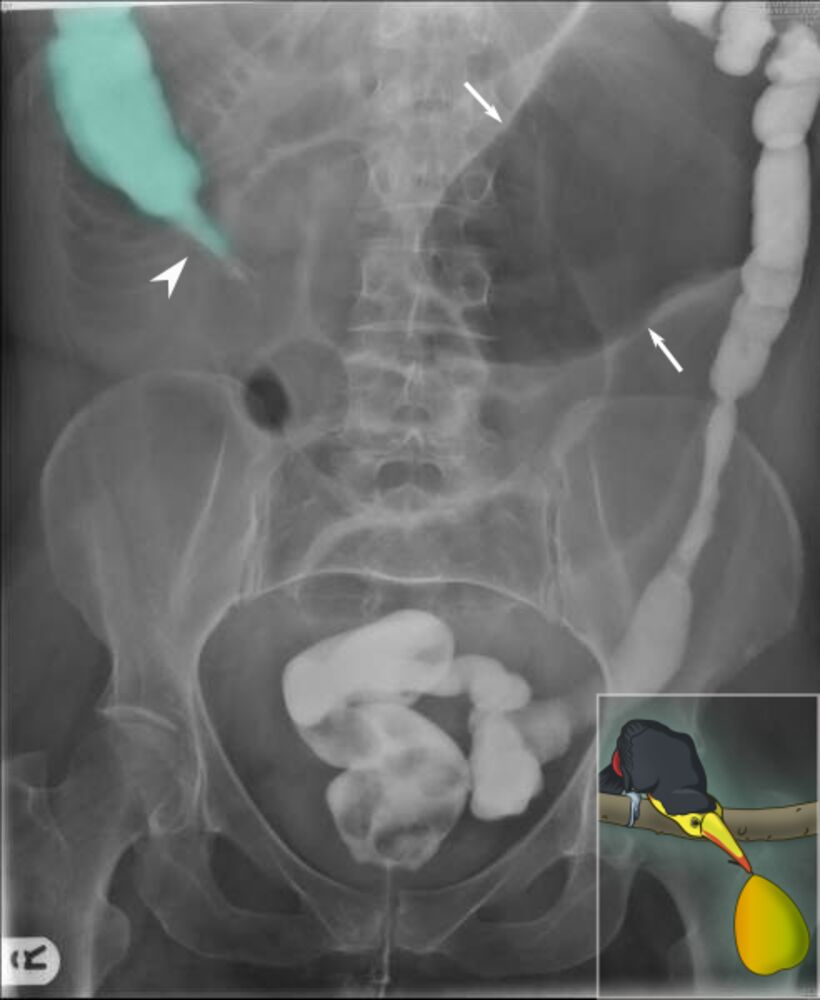

- Contrast radiography with enema (bird’s beak appearance in volvulus, Apple core sign in colonic malignancy)

| Sigmoid Volvulus | |

| Risk Factors |

|

| Clinical Presentation |

| Imaging |

| Management |